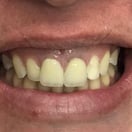

Coroa instalada em boca

As coroas ou lentes de porcelana também tem ampla indicação em casos unitários : dentes fraturados, escurecidos após tratamentos de canal, alterações de forma e manchas que não respondem ao clareamento, são exemplos de situações em que precisamos harmonizar esse novo dente com os vizinhos.

Espelhar um dente vizinho com uma nova coroa ou faceta de porcelana, é um procedimento altamente técnico, que requer a habilidade e experiência de um dentista estético e de um laboratório qualificado.